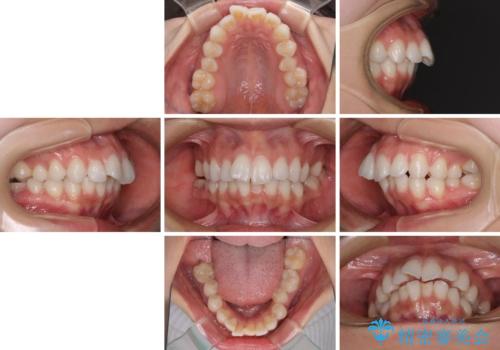

- 口元の突出感を気にして来院された患者様です。

左右ともに奥歯の咬み合わせに問題があり、上顎臼歯が前方位にある状態で、結果として上顎前歯全体が前方位かつ叢生になっていました。

補助装置を用いて上顎歯列全体を後方に移動させ、下顎は左右で抜歯する小臼歯を変えることで、左右の咬み合わせをより理想的な位置となるように計画しました。